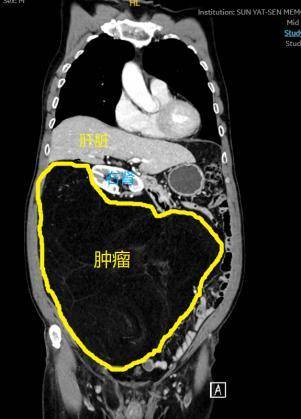

CT和MR检查结果提醒,陈大爷腹腔右侧腹膜后一个巨大的脂肪性肿瘤几乎占据整个腹腔,将原本位于腹腔右侧的右肾和右侧输尿管、升结肠、小肠等脏器全部推压到左侧腹腔,肝脏由于肿瘤推压向上抬起,压迫膈肌和右侧肺脏,肝右叶由于肿瘤推压也逐渐萎缩变小,肿瘤向下进入盆腔,并通过右侧腹股沟内环口向外挤压形成一个疝样结构。

影像检查显示,“巨无霸”肿瘤几乎占据整个腹腔。 受访者供图